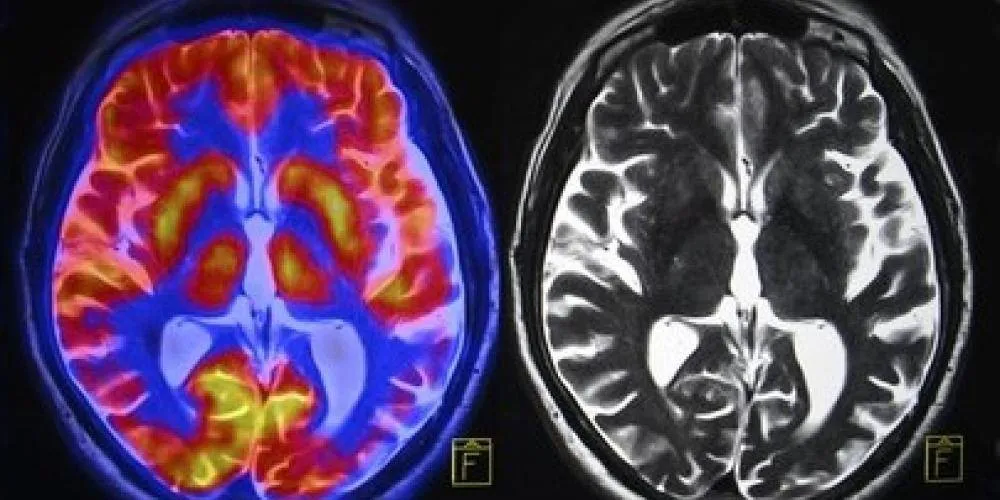

brain-scan-260nw-273127421

Uit een nieuwe analyse van ruim 4000 hersenscans, van baby tot negentiger, komt een verrassend strak patroon naar voren. De bedrading van de hersenen doorloopt vijf fasen, gescheiden door vier keerpunten: rond 9, 32, 66 en 83 jaar. De onderzoekers spreken van “topologische keerpunten”: momenten waarop de manier waarop hersengebieden met elkaar verbonden zijn, echt van richting verandert.